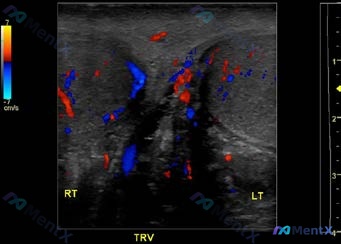

看到一个很典型的阴囊急症超声病例,整理了一下分析思路,分享给大家。 --- 病例影像核心信息 这是一份双侧附睾的多普勒超声对比(纵轴+横轴): - 右侧(RT):附睾大小形态正常,实质回声均匀,仅见少量点状血流信号。 - 左侧(LT):附睾明显肿大,轮廓饱满,实质回声不均匀(呈低回声伴细小斑点);彩...